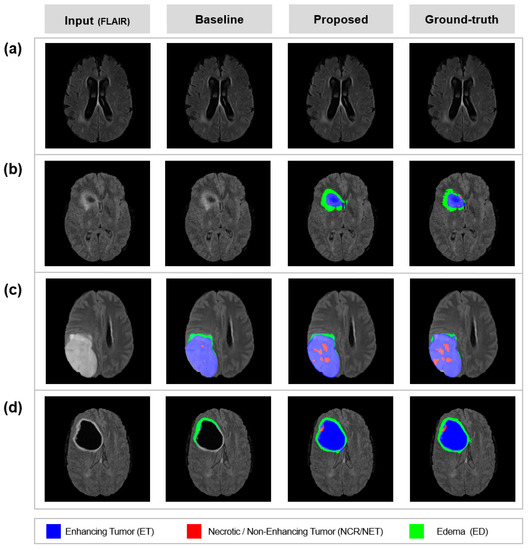

Figure 5.

Uncertainty exploitation results: Automatic segmentation results by baseline/proposed method and manual segmentation by experienced neurologists (ground-truth). The images are subsequent results of Figure 4. The proposed method can exploit uncertainty maps to perform brain tumor segmentation. (a) scans with no tumor. (b) scans with ET and ED. (c) scans with all lesions. (d) scans with all lesions.

A qualitative comparison between the baseline and the proposed model is shown in Figure 5. The segmentation results of the model with UAM (proposed) corresponded well with ground truth. The model with UAM was effective in reducing significant errors, such as ET (Figure 5a,d). Moreover, tiny and confusable lesions such as NCR/NET were well predicted by using UAM (Figure 5c). The well-predicted lesions without UAM were maintained well even with UAM (Figure 5b).